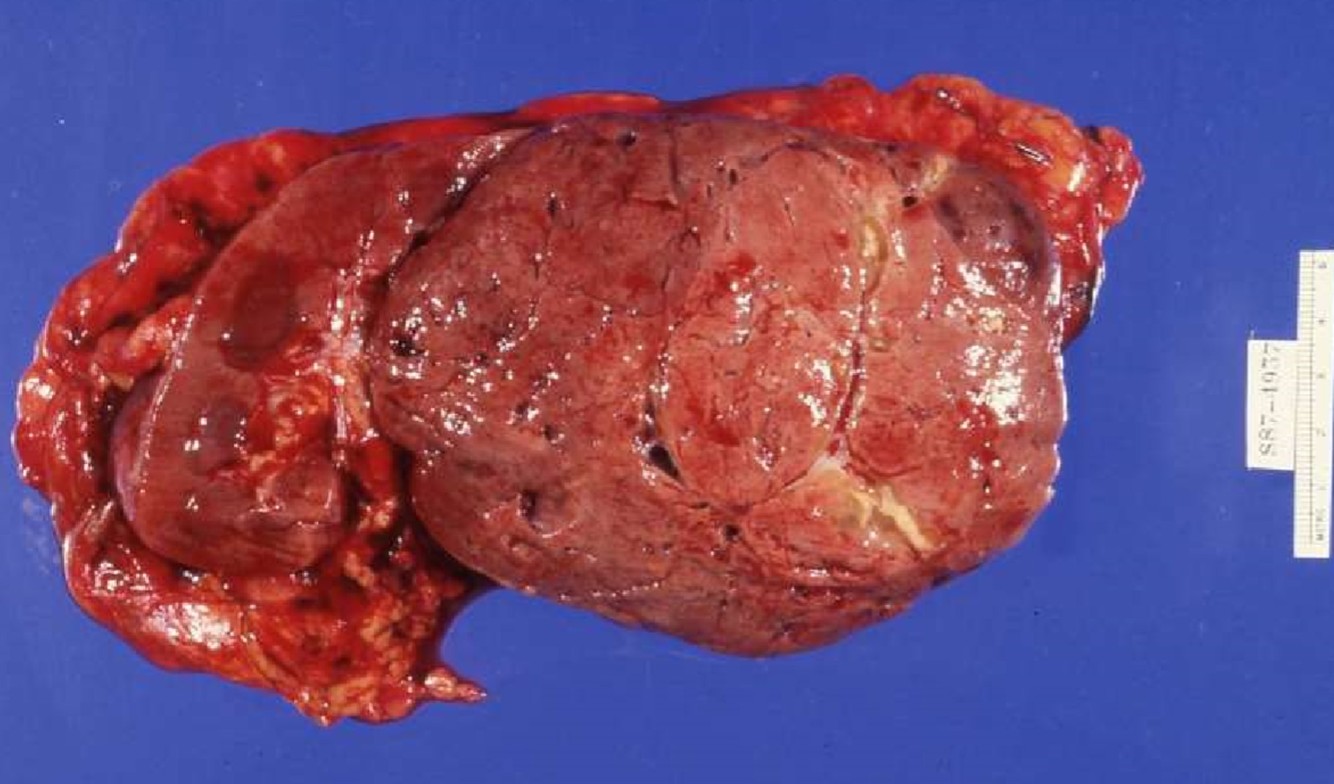

RENAL ONCOCYTOMA

- Gross:

- Circumscribed, not encapsulated

- Mahogany brown, central scar

- No gross necrosis